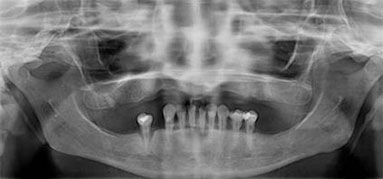

锥形束平板CT:

360°3D口腔透视

CT数据+种植医生

+3D种植模拟软件

智能导航,3D种植导板定位

骨量严重萎缩的情况下,利用斜行植体等技术,避免植骨手术。